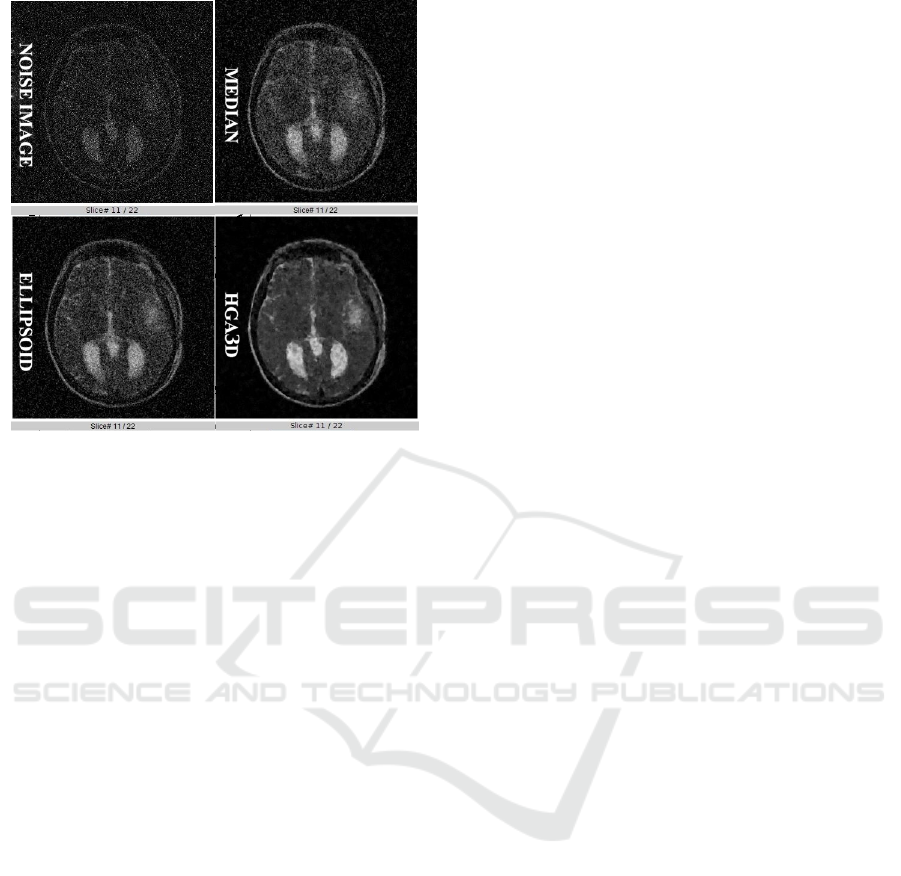

some literature attenuation methods: BM4D (Maggi-

oni et al., 2013), 3D median filter (Jiang and Crookes,

2006) and ellipsoid (Yang et al., 2008).

Each individual of the population corresponds to

an image initially restored by one of these three met-

hods and the others individuals of the population are

created through the application of different mutation

operators in the initial image. HGA3D evolves the

entire population during a determined amount of time

and at the end the best individual is returned as the

restored image.

Based on the researchs carried out and described,

a genetic algorithm based on BM4D, 3D median and

ellipsoid was developed.